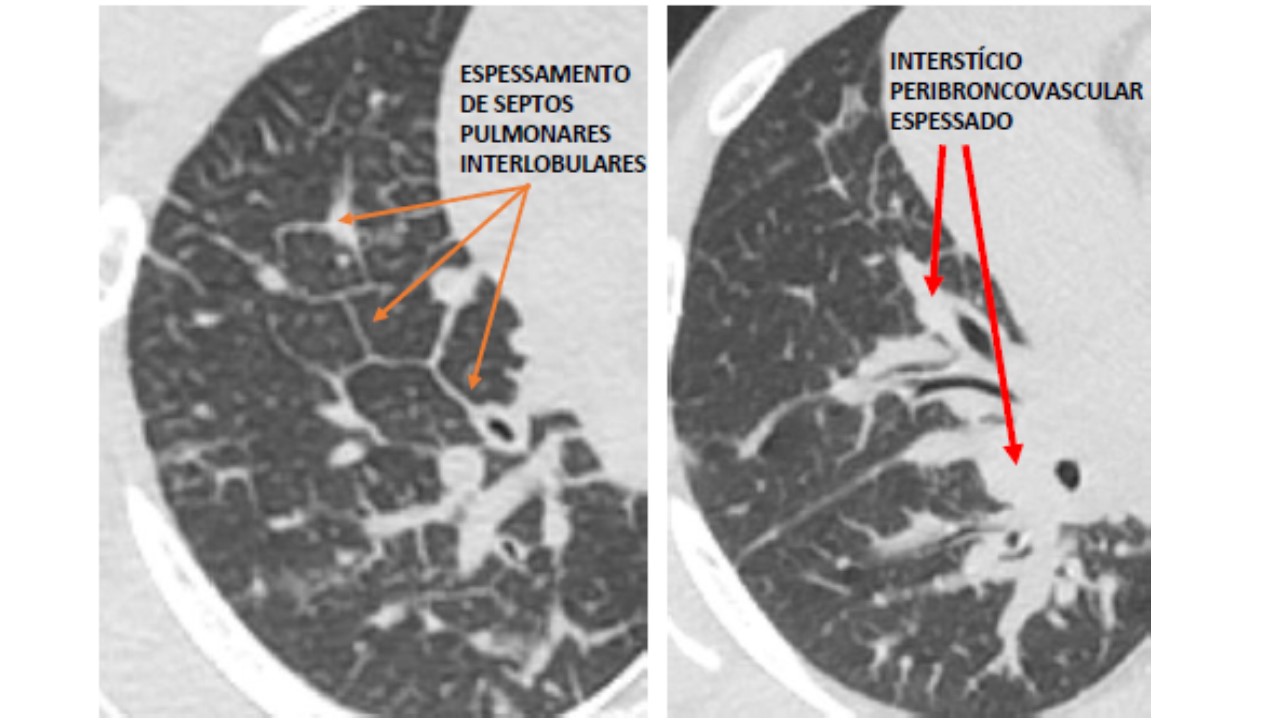

LINFANGIOMATOSE PULMONAR DIFUSA: IMPORTÂNCIA DO SISTEMA LINFÁTICO NO TÓRAX

13/08/2020 09:58

Ler Mais